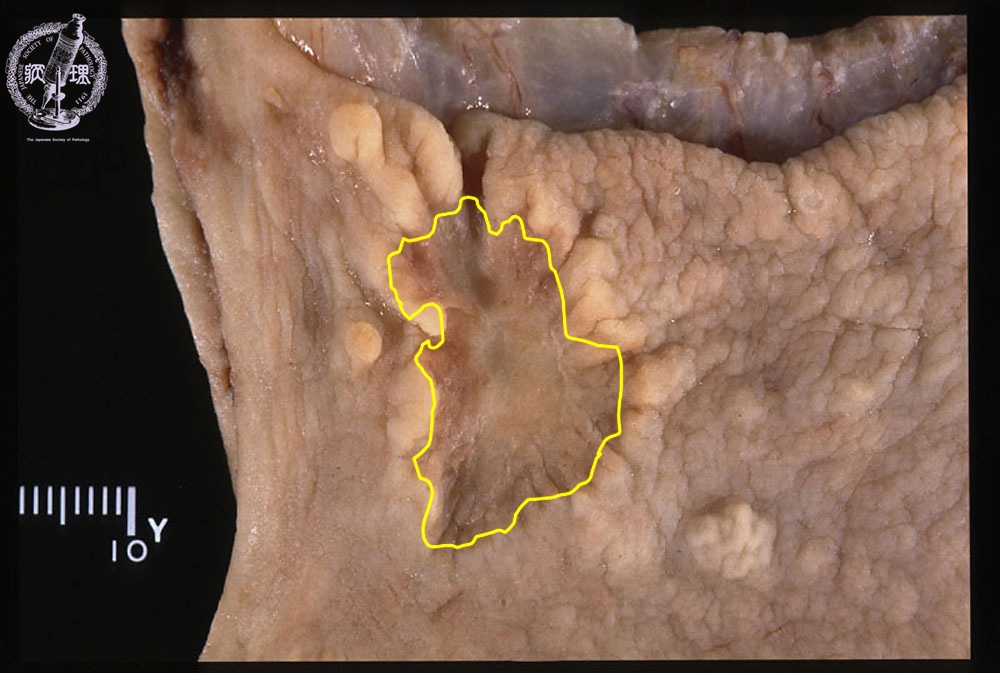

- ★(8)Stomach cancer(early gastric cancer)

Gross appearance: Early (Type 0-IIc) carcinoma measuring 28 x 18 mm and arising in the anterior wall of the gastric antrum. The interface with non-dysplastic mucosa is undulating and the later shows reactive elevation. The lesion has a brownish, depressed and granular surface.